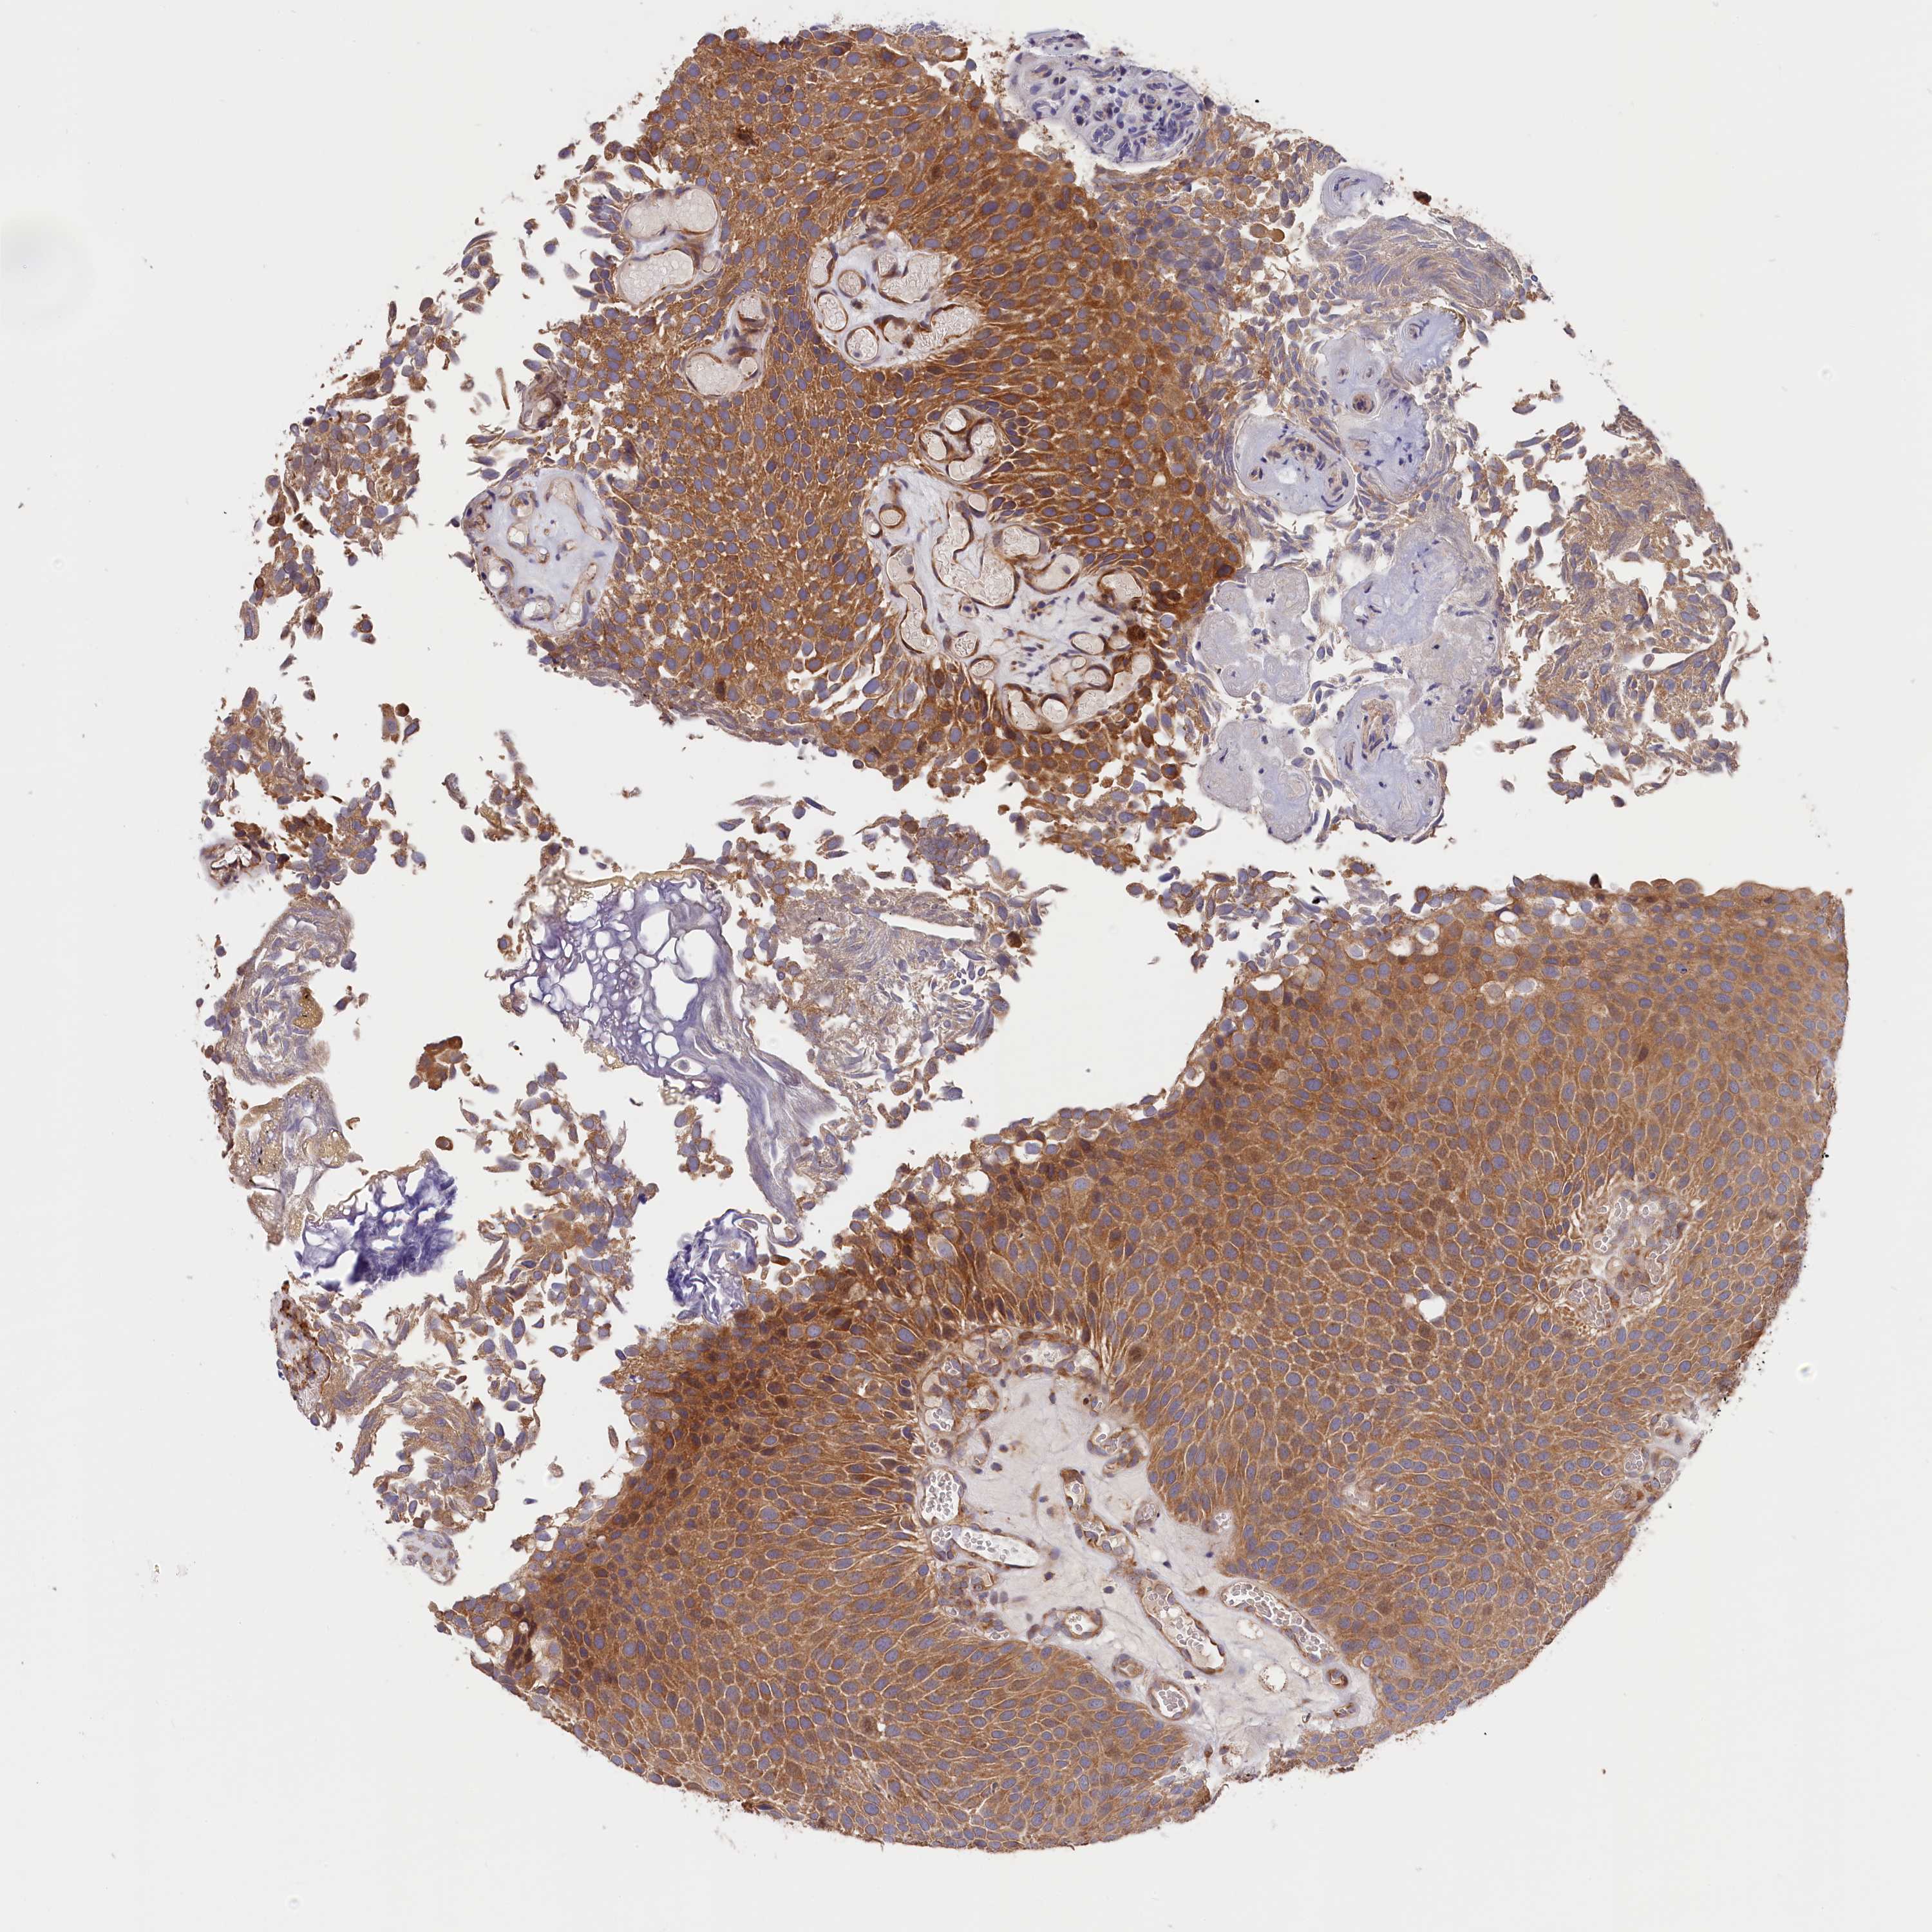

UROTHELIAL CANCER - Protein expressioni

A mouse-over function shows sample information and annotation data. Click on an image to view it in a full screen mode. Samples can be filtered based on level of antibody staining by selecting one or several of the following categories: high, medium, low and not detected. The assay and annotation is described here.

Note that samples used for immunohistochemistry by the Human Protein Atlas do not correspond to samples in the TCGA dataset.

Antibody stainingi

Antibody staining in the annotated cell types in the current human tissue is reported as not detected, low, medium, or high, based on conventional immunohistochemistry profiling in selected tissues. This score is based on the combination of the staining intensity and fraction of stained cells.

Each image is clickable and will lead to virtual microscopy that enables deeper exploration of all samples and also displays staining intensity scores, fraction scores and subcellular localization as well as patient and tissue information for each sample.

Antibody HPA041515

Antibody HPA041835

Urothelial carcinoma, High grade

Urothelial carcinoma, Low grade